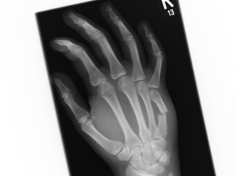

Röntgenbilder